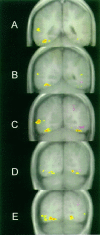

Twelve normal subjects viewed alternating sequences of unfamiliar faces, unpronounceable nonword letterstrings, and textures while echoplanar functional magnetic resonance images were acquired in seven slices extending from the posterior margin of the splenium to near the occipital pole. These stimuli were chosen to elicit initial category-specific processing in extrastriate cortex while minimizing semantic processing. Overall, faces evoked more activation than did letterstrings. Comparing hemispheres, faces evoked greater activation in the right than the left hemisphere, whereas letterstrings evoked greater activation in the left than the right hemisphere. Faces primarily activated the fusiform gyrus bilaterally, and also activated the right occipitotemporal and inferior occipital sulci and a region of lateral cortex centered in the middle temporal gyrus. Letterstrings primarily activated the left occipitotemporal and inferior occipital sulci. Textures primarily activated portions of the collateral sulcus. In the left hemisphere, 9 of the 12 subjects showed a characteristic pattern in which faces activated a discrete region of the lateral fusiform gyrus, whereas letterstrings activated a nearby region of cortex within the occipitotemporal and inferior occipital sulci. These results suggest that different regions of ventral extrastriate cortex are specialized for processing the perceptual features of faces and letterstrings, and that these regions are intermediate between earlier processing in striate and peristriate cortex, and later lexical, semantic, and associative processing in downstream cortical regions.